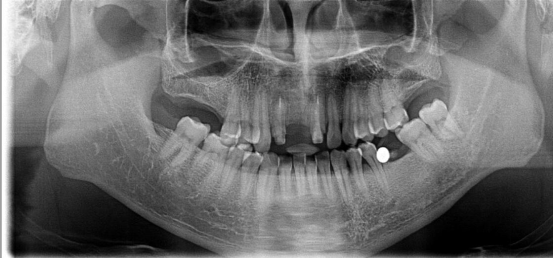

外傷性牙缺失修復(fù)案例

20歲的林先生還在上大學(xué),喜歡踢足球。但是在一次學(xué)校足球賽場(chǎng)上摔倒把牙齒給磕掉了。發(fā)生這樣的意外把林先生嚇了一跳,當(dāng)即在同學(xué)的推薦下來到科爾口腔就診。

“像這種外傷性牙缺失其實(shí)很常見,手術(shù)起來也很簡(jiǎn)單?!眲⒈笤淌诳戳讼铝窒壬难例X后,安撫林先生不需要太擔(dān)心:“種上牙齒后無(wú)論外形還是使用感都跟真牙無(wú)異,完全不影響你以后的生活?!?

林先生的手術(shù)進(jìn)行得很快,牙齒恢復(fù)后還特地帶了老家特產(chǎn)來感謝劉斌元教授:“牙齒掉的時(shí)候就覺得我完蛋了,缺牙了。但是劉斌元教授很快就解決了我的問題,而且現(xiàn)在用起來真的跟以前沒有兩樣,不過下次踢球我會(huì)小心的?!?